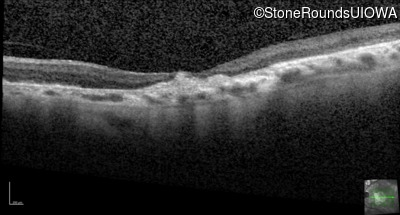

Optical Coherence Tomography - Left - 20/80

Exemplar / OCT Stack

Infrared Fundus Photograph - Right - 20/125 -2